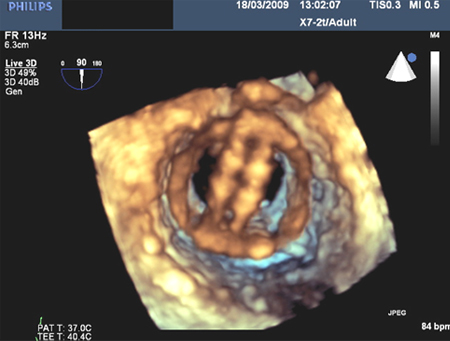

[Figure caption and citation for the preceding image starts]: Mitral valve P2 leaflet prolapse: 3D viewFrom the collection of Prakash P. Punjabi [Citation ends].

[Figure caption and citation for the preceding image starts]: Prosthetic mitral valve with intermittent mitral regurgitationFrom the collection of Prakash P. Punjabi [Citation ends].